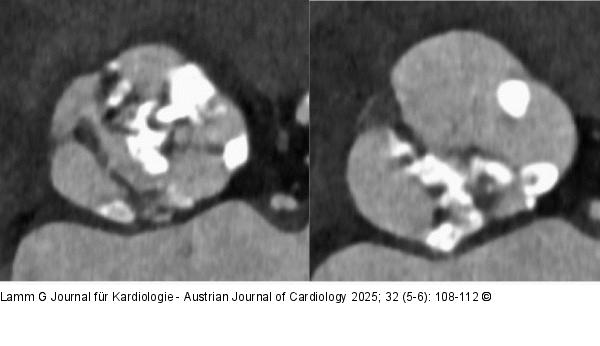

Abbildung 1: Aortenklappe Bikuspide Aortenklappe mit stark kalzifizierter Raphe in der Multislice-CT |

Abbildung 1: Aortenklappe

Bikuspide Aortenklappe mit stark kalzifizierter Raphe in der Multislice-CT |